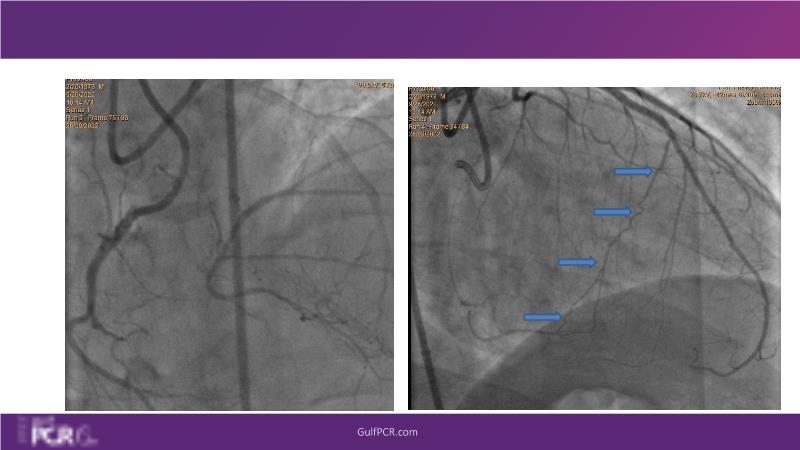

Thanks to the recorded complex CTO case shared in this session, learn how to perform ultra-low contrast PCI, learn what skills are required and tools available to perform ultra-low contrast coronary interventions in CTO, and become aware of the importance of relying on less contrast injections to guide PCI in complex CTO cases.